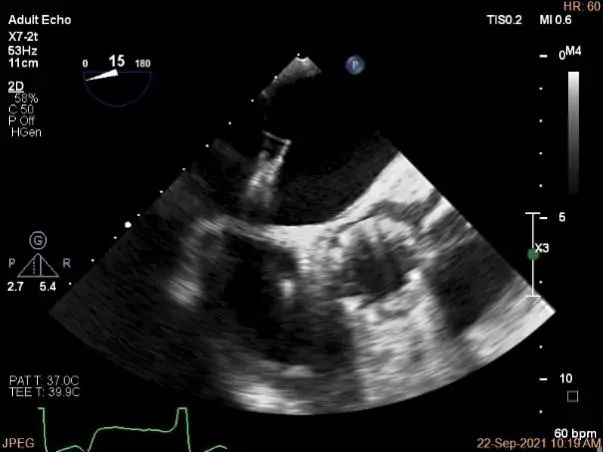

房间隔穿刺点选择

穿刺高度:4.08cm

穿刺高度:4.3cm